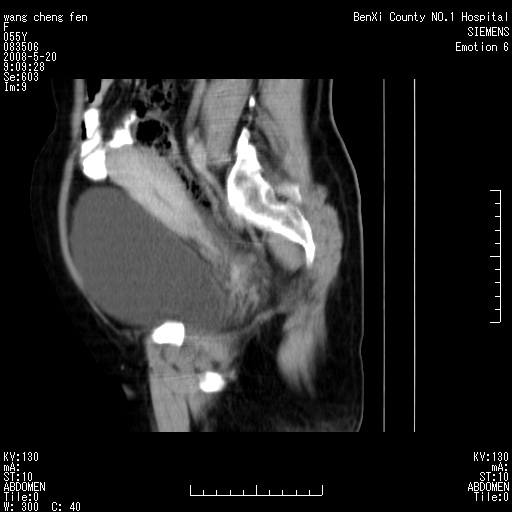

女、绝经后阴道流血3个月

左侧附件区可见一囊性占位,边缘清楚,内可见不规则形软组织影 ce:囊壁及内部可见强化 考虑 卵巢囊腺瘤

左侧附件区巨大囊实性病灶,边缘光整,病灶囊壁较厚,增强示囊壁及实性部分明显强化,强化呈度与宫体实质大致相同,宫腔积液征像,未见盆腔积液等其他异常,考虑左侧卵巢囊腺癌,不除外囊腺瘤及浆膜下肌瘤坏死

左侧附件区巨大囊实性病灶,边缘光整,病灶囊壁较厚,增强示囊壁及实性部分明显强化,强化呈度与宫体实质大致相同,宫腔积液征像,未见盆腔积液等其他异常。绝经后阴道流血3个月,结合病史左侧卵巢囊腺癌首先考虑,宫腔扩大不除外累及。期待结果。

支持浆膜下子宫肌瘤.之前由于网络原因未看全图片,现在重看,宫颈见一类圆形低密度影,增强轻度强化,低于肌层强化,宫腔扩大,考虑宫颈癌伴宫腔积液可能性大.

囊实性肿块分隔厚度较大,厚薄不均,增强实性成分明显强化,有不规则阴道流血,卵巢囊腺癌可能性大。

1,宫颈部占位,宫颈癌?2,左侧附件区囊实性占位,界较清,实质部分强化明显。考虑浆膜下或阔韧带肌瘤囊变可能大。囊腺类肿瘤不除外。